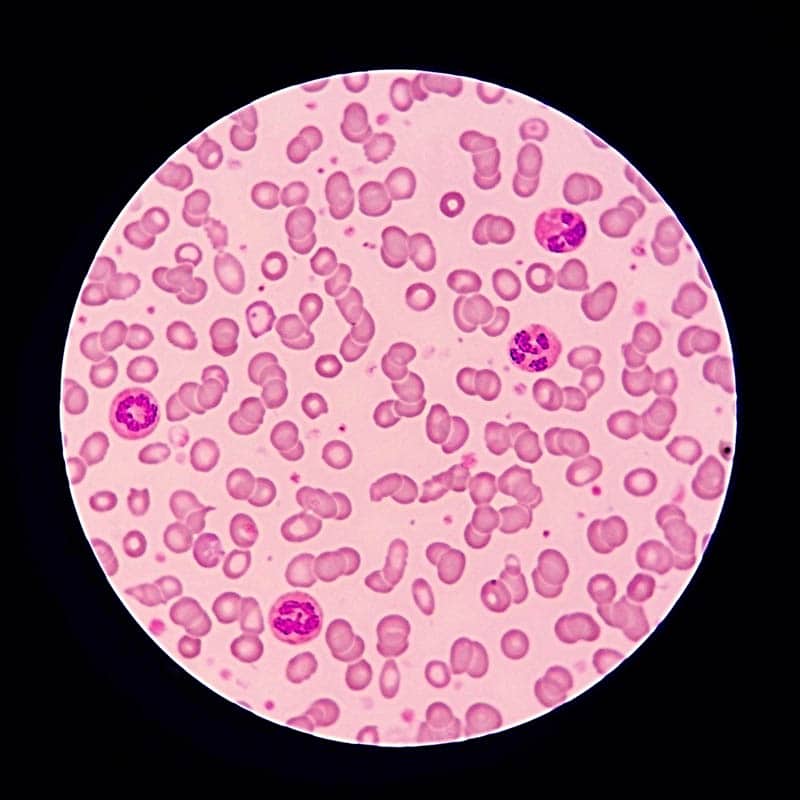

What Do Cells Look Like Under A Microscope Types Parts FAQ

https://opticsmag.com/wp-content/uploads/2022/11/white-blood-cells-seen-on-a-microscope_Tewan-Banditrakkanka_Shutterstock.jpg

What Do Cancer Cells Look Like Under A Microscope The Interesting